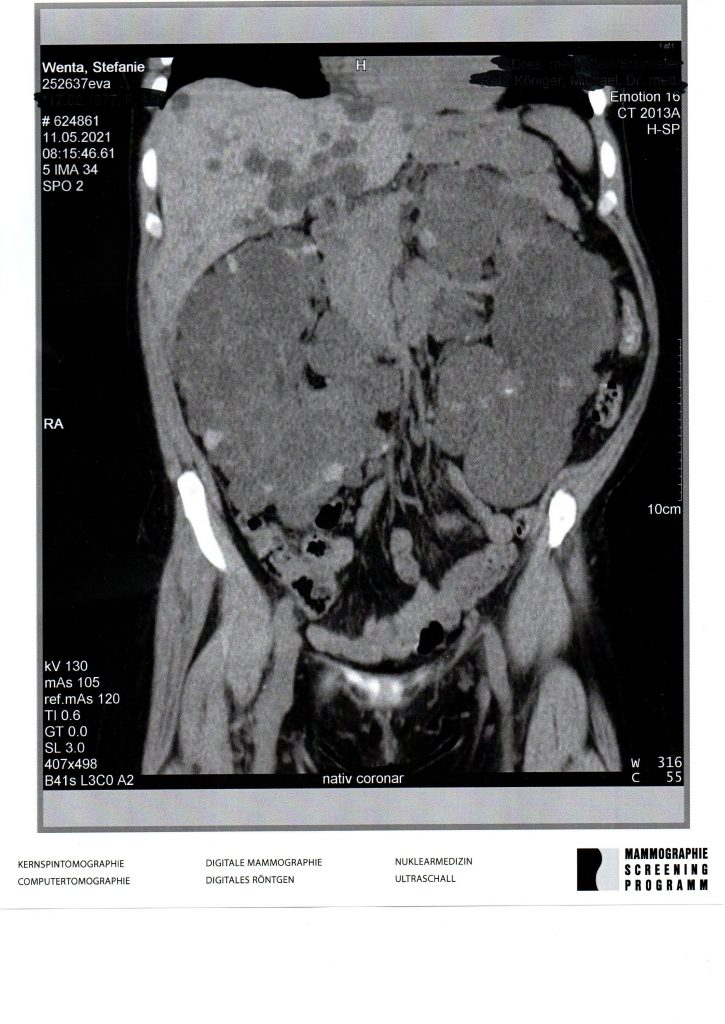

Nein – um zu erkennen, dass das keine gesunden Nieren sind, muss man nicht zig Semester Medizin studiert haben! Heutige CT-Aufnahme (ohne Kontrastmittel, weil das meine Nieren nicht mehr mitmachen). Sehr viel weiter wachsen können die irgendwie ja nicht mehr, oder doch????!!!

Ein Leidensgenosse. Meine füllen auch den gesamten Bauchraum aus. Egal was kommt…Alles Gute weiterhin…